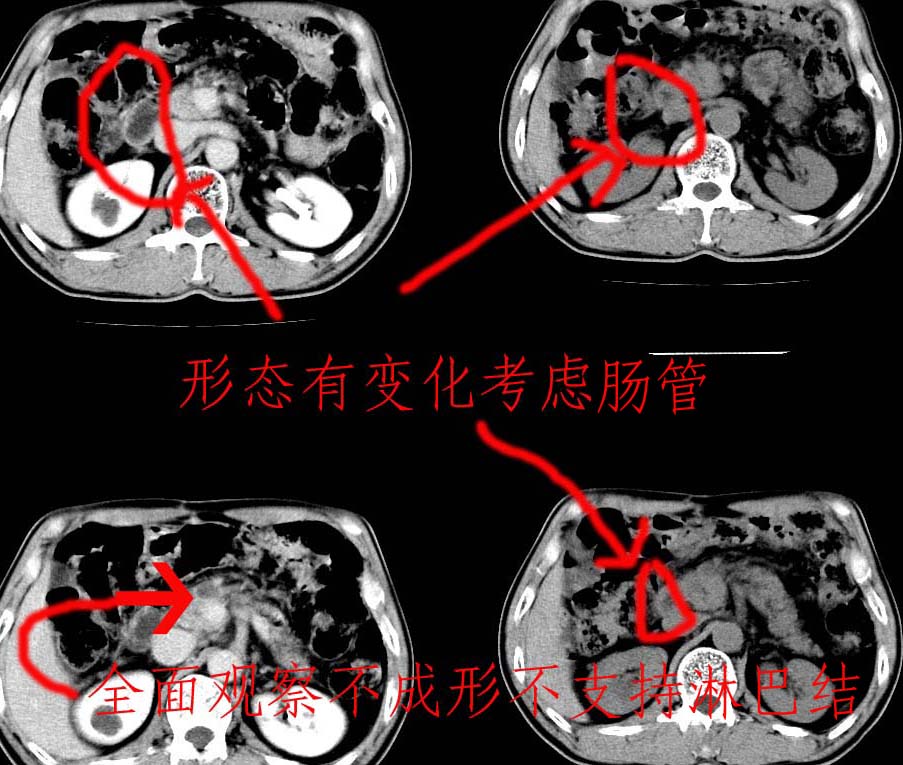

标题: 做了个图方便探讨。

不知道楼主说得是那个?

一个形态变化大应该是肠管。

另一个上下观察不成形,强化也不符合淋巴结表现故考虑术后改变。